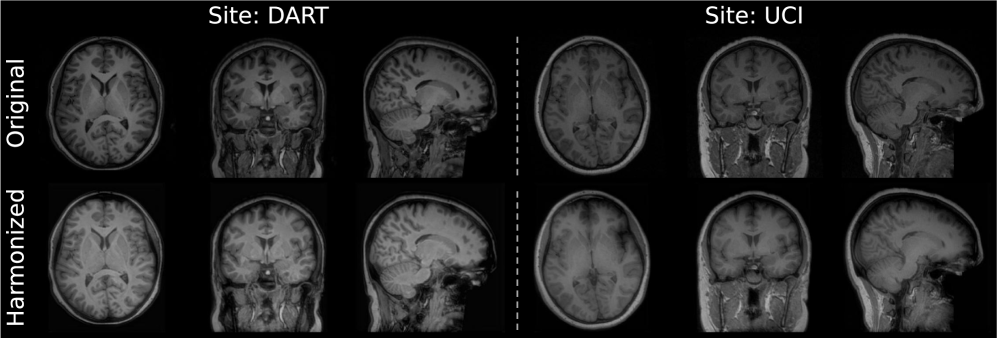

Figure 10: Zero-shot global harmonization on unprocessed MRIs. Visualization of raw inputs (Top) vs. globally harmonized outputs (Bottom) for Site DART and Site UCI across all three views (Axial, Coronal, Sagittal).

5.3 Influence of Preprocessing Steps

Standard harmonization protocols [29, 5, 53] typically treat image-level harmonization as the final stage of a preprocessing pipeline, operating on MRI volumes that have been skull-stripped, bias-corrected, and registered to standard templates (e.g., MNI). To demonstrate robustness, we evaluate the zero-shot generalization by applying the frozen Stage I Global Harmonizer (trained on the preprocessed/skull-stripped data from our main experiment) directly to raw, unprocessed MRIs from DWI-THP test set. The visualization in Fig. 10 shows the frozen model successfully projects the unprocessed MRIs from two sites into a unified intensity domain. Despite never observing skulls or background noise during training, it effectively harmonizes the brain tissue contrast while preserving the unseen non-brain structures, demonstrating MMH’s ability to operate on raw, native-space images without extensive preprocessing.